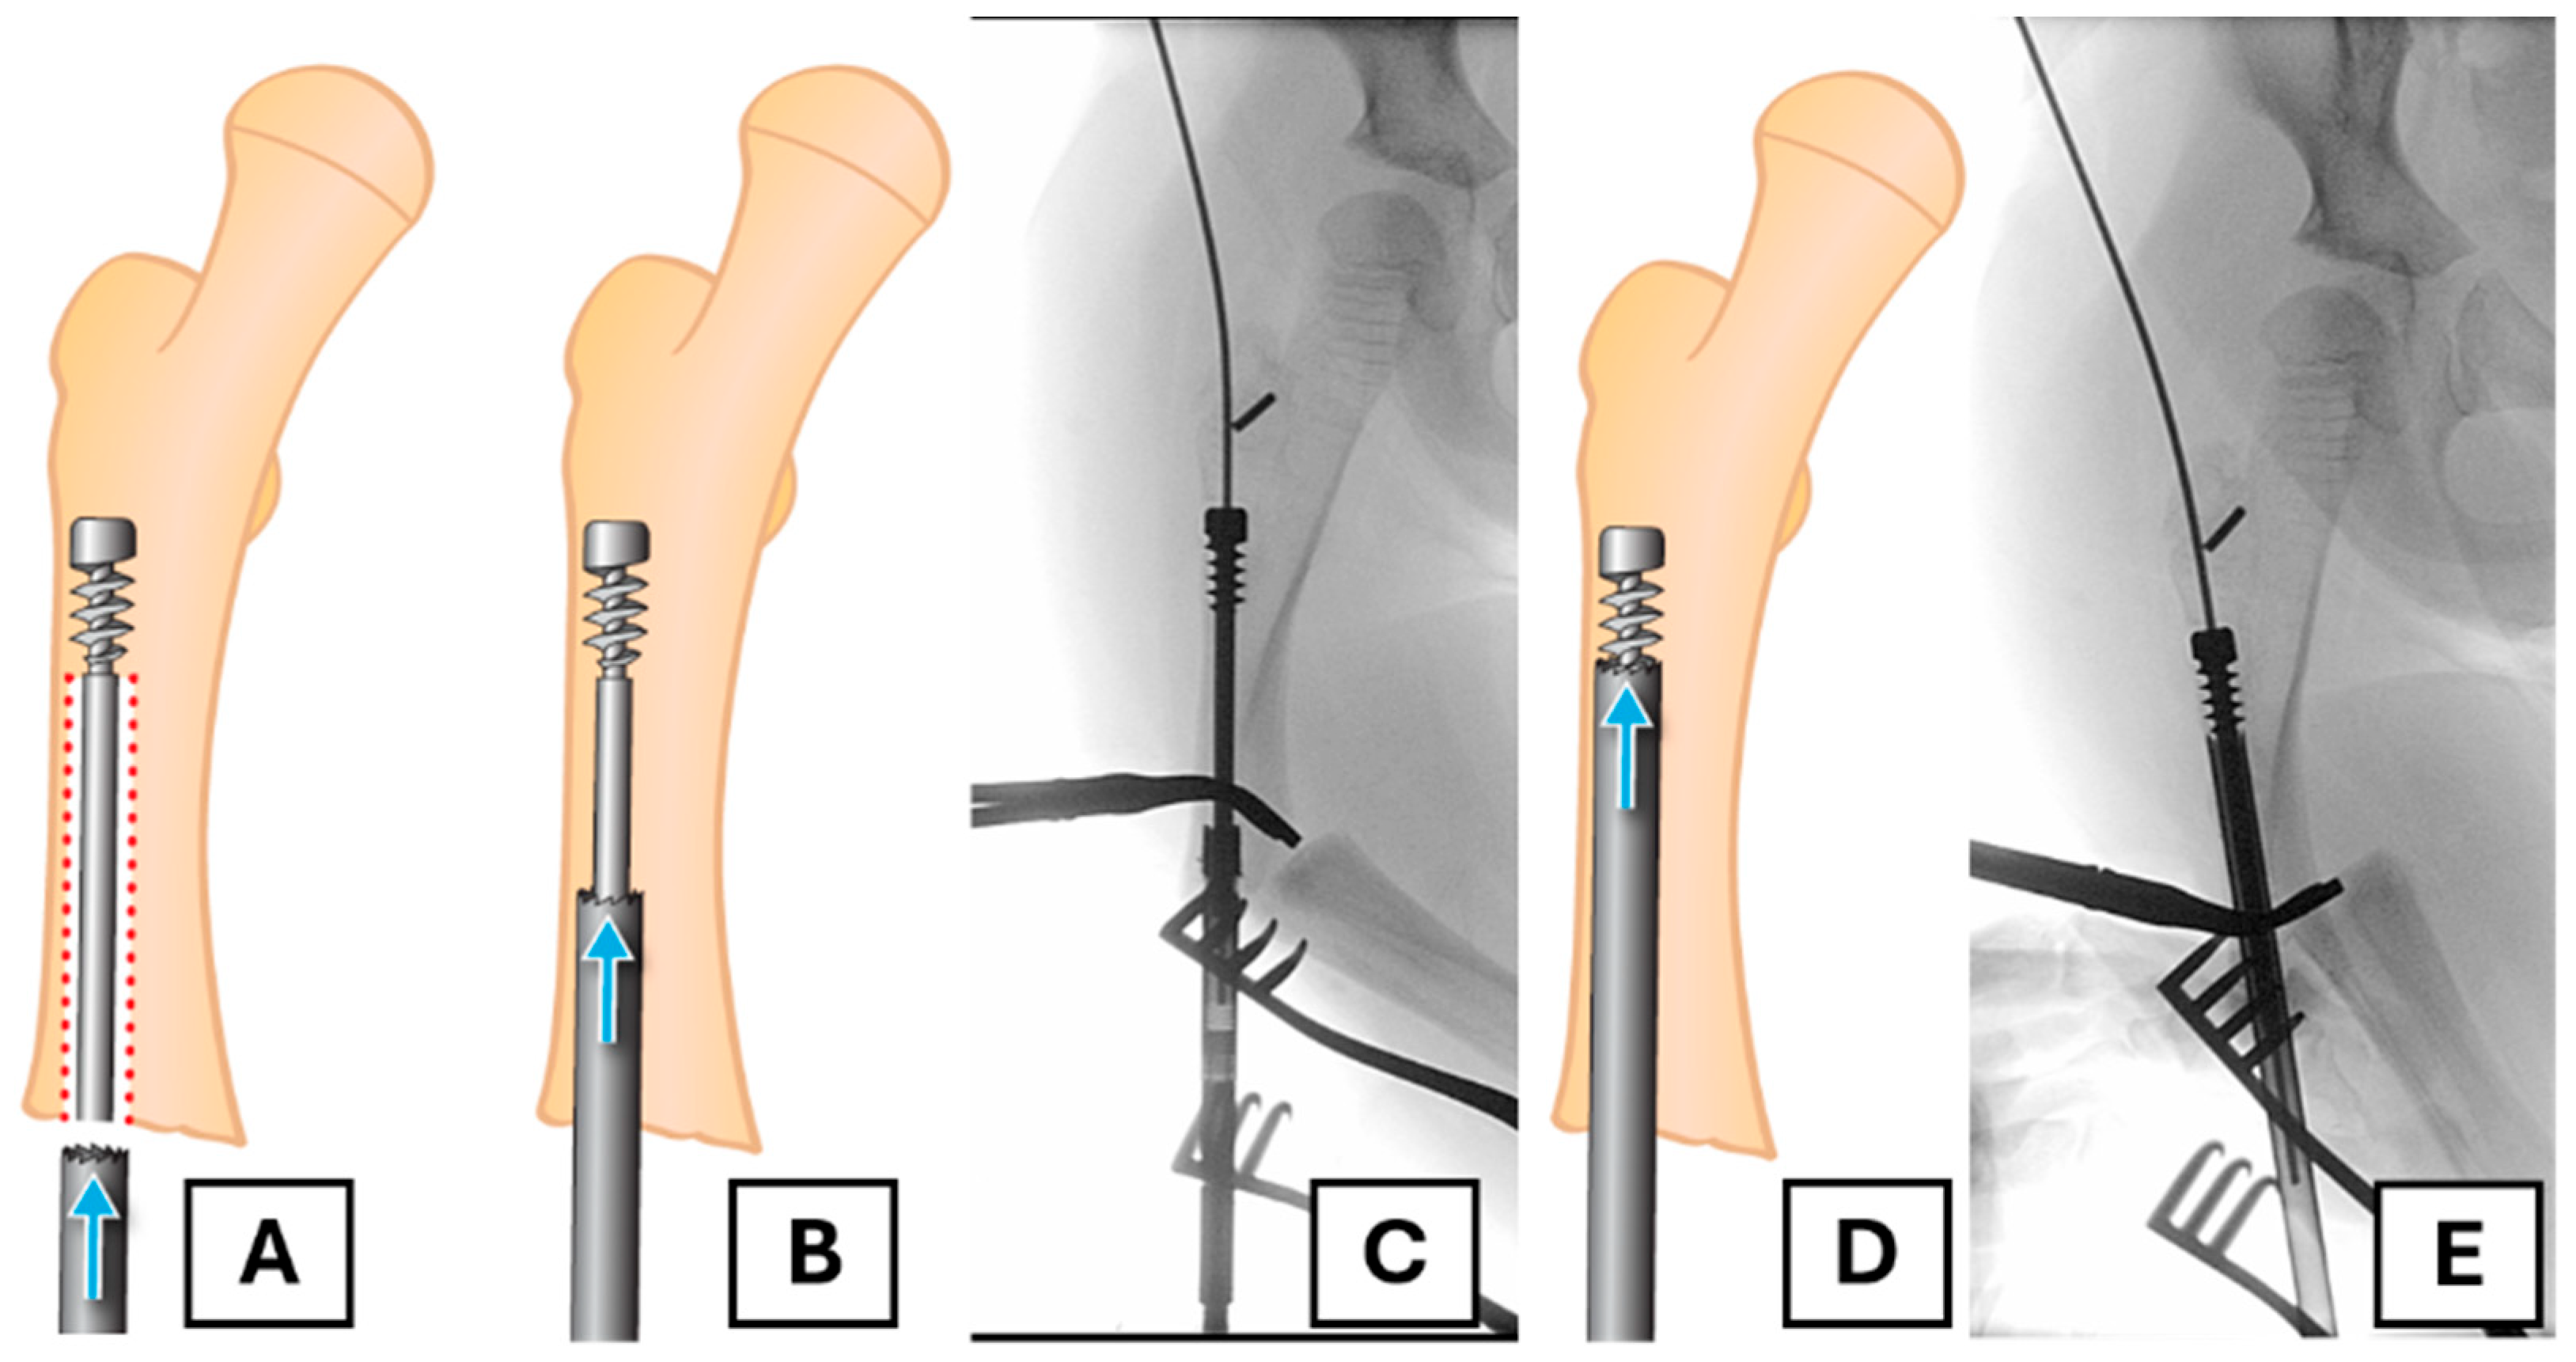

4.4. Revision Rod Placement

Once successful removal is completed, the placement of a revised FD rod is undertaken in a standard open osteotomy fashion. There may be a pseudocortex present in the proximal segment, dividing the previous rod tract from the desired line of exit through the greater trochanter. Accurate placement of the guidewire can be challenging, as it tends to follow the previously created channel and may be pushed medially by the sclerotic edge (Figure 5A,B). To solve this problem, curettage or drilling may be necessary to allow the guidewire to follow the appropriate path through the proximal segment to its exit point. We used a 2 mm drill bit to create a pathway in the desired line, creating access for the guidewire (Figure 5C–E).

Figure 5. Establishing the correct path for the revision rod. (A,B) Illustration and corresponding radiograph showing the guidewire’s trajectory being deflected medially by the sclerotic pseudocortex of the old rod tract. (C) A drill is used to create a new pathway through the blocking bone. (D,E) Illustration and radiograph confirming the correct trajectory of the guidewire towards the greater trochanter apex.